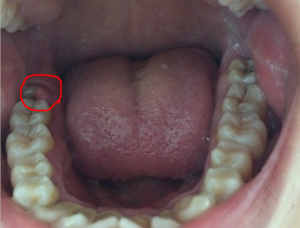

牙齦息肉表現2、存在的息肉可通過手術切除的。如果是上火後出現的疙瘩包塊。注意是否存在根尖周炎形成的。對應採取治療措施。

6、手術治療對於一些牙齦增生嚴重的病例,雖經以上治療,也不能完全消退,此時需用手術切除並修整牙齦外形。但手術要選擇在全身病情穩定時進行.術後若不停藥和保持口腔衛生,仍易復發。

四、手術治療對於一些牙齦增生嚴重的病例,雖經以上治療,也不能完全消退,此時需用手術切除並修整牙齦外形。但手術要選擇在全身病情穩定時進行.術後若不停藥和保持口腔衛生,仍易復發。